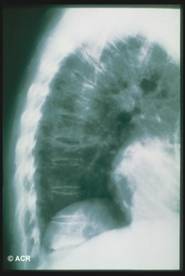

Il 30% della massa ossea viene persa prima che l'osteoporosi possa essere evidenziata dalle radiografie;

Evidenzia le fratture.

Reperti radiografici

Lisi ossea: riflette l'aumentata attività osteoclastica;

Sclerosi: riflette l'aumentata attività osteoblastica;

Aumento volumetrico dell'osso;

Lesioni litiche a "fiamma": riscontrabili a carico delle ossa lunghe;